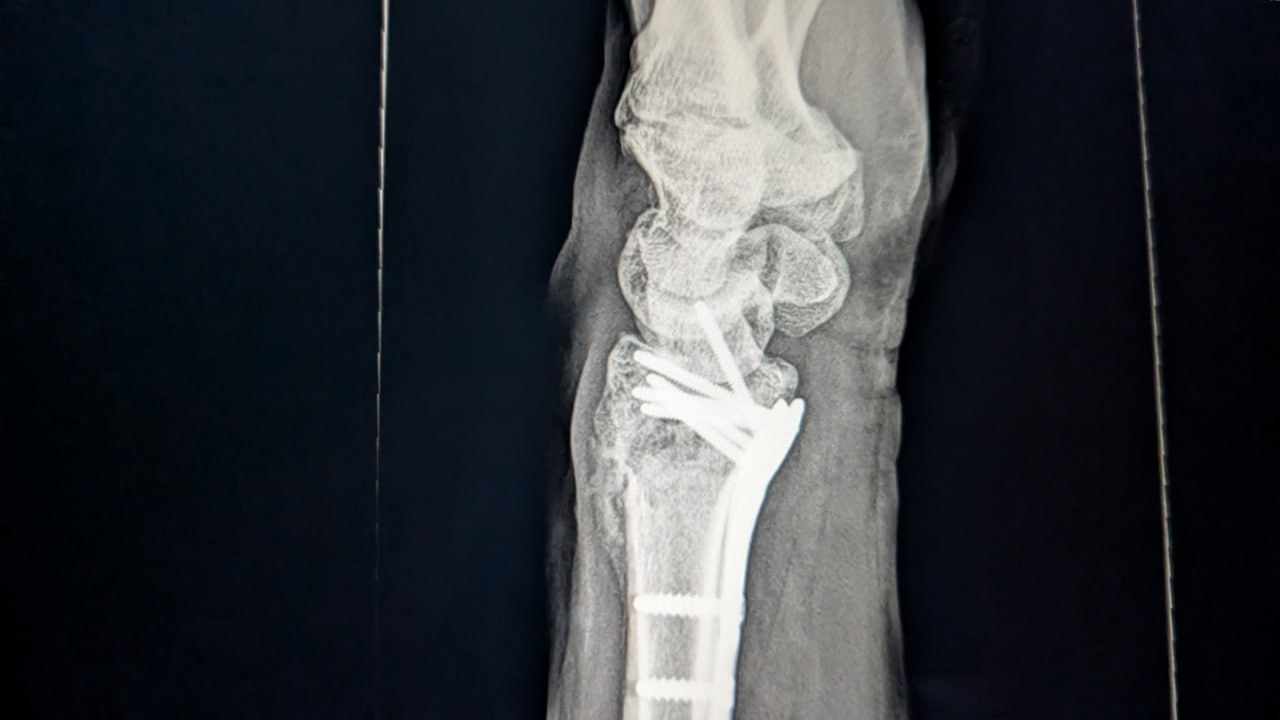

The fracture required surgical intervention — a procedure that left Charlie's wrist reinforced with a metal plate and screws. For most people, that kind of repair means a long, slow road back to full mobility.

Charlie's recovery timeline told a different story. Just four weeks after surgery, he had regained a surprising level of motion and flexibility in his wrist — well ahead of what his physical therapist typically sees in comparable cases. By seven weeks post-surgery, he was back on the mountains: Nordic skiing, moving through his training regimen, pacing well ahead of average recovery expectations.